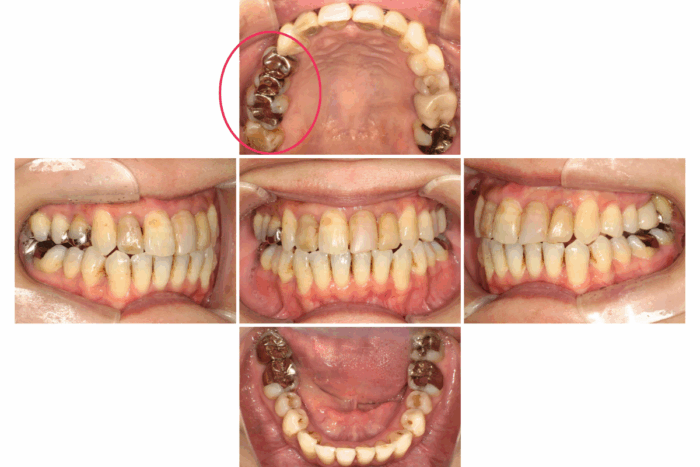

患者さま:30代女性/左上4・5・6番にメタルブリッジ

主訴:歯のガタつき・かみ合わせが反対

矯正治療のために上下左右4本抜歯する必要がありました。そのため、抜歯する歯のうち1本は、ブリッジを分割しポンティック部分(ブリッジの真ん中の人工歯のこと)を除去して代用しました。ワイヤー矯正で歯並びとかみ合わせを改善しました。

- 【症例詳細】

- 主訴:ガタガタと受け口が気になる

- 診断名:叢生・反対咬合

- 初診時年齢:32歳

- 使用装置:ホワイトワイヤー矯正

- 抜歯部位:上顎右側第二小臼歯、下顎右側第二小臼歯、下顎左側第一小臼歯

- 治療期間:2年7ヶ月

- 費用:¥750,000(税込¥825,000)

- リスク・副作用:痛み、歯根吸収、歯肉退縮、むし歯、後戻り